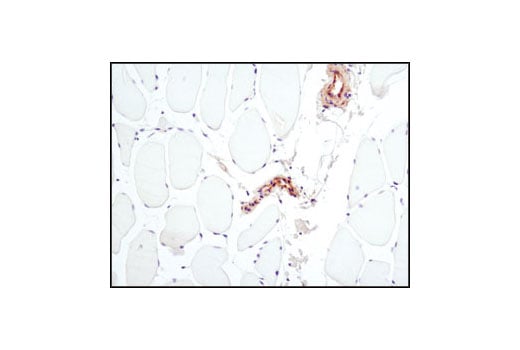

Immunohistochemical analysis of paraffin-embedded human skeletal muscle using PKM2 (D78A4) XP® Rabbit mAb. Note the lack of staining in the skeletal muscle cells which do not express PKM2 while vessels within the tissue stain positively.

Immunohistochemistry Image 3: PKM2 (D78A4) Rabbit Monoclonal Antibody